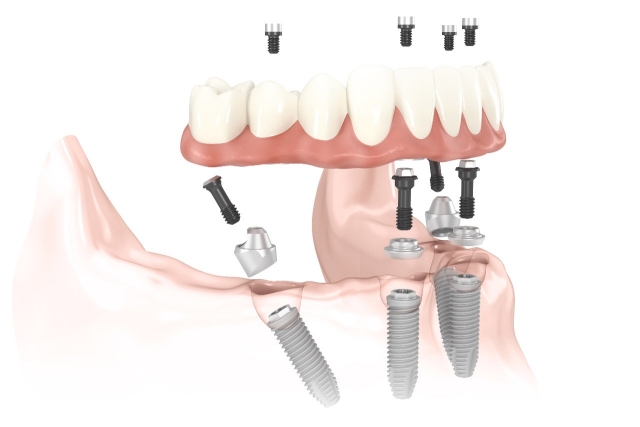

所謂 All-on-4 或 All-on-6 全口重建,其實就是我們用 4 根或 6 根植體,把一整排的假牙固定在上面,對於那些牙齒缺失超過 10 到 12 顆的患者,All-on-4/6 技術提供了一個高效的解決方案,利用上、下顎的黃金三角區域,也就是骨量最高的區域中,選擇四支牙根強化補骨,就能安裝整副固定式假牙,大幅縮短了傳統補骨癒合的等待期。

此外,對於牙肉萎縮嚴重的患者,All-on-4/6 也是理想選擇,這種技術使用的假牙可以模擬自然牙齦的外觀,提供完美的牙齒和牙齦比例,增強美感,其功能與效果遠勝於傳統的活動假牙。